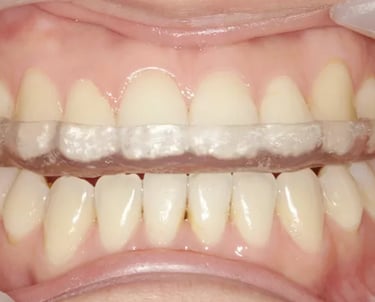

Se utilizan dispositivos que se colocan en la boca para estabilizar la mandíbula y aliviar el dolor y la disfunción.

Colocación de férulas oclusales